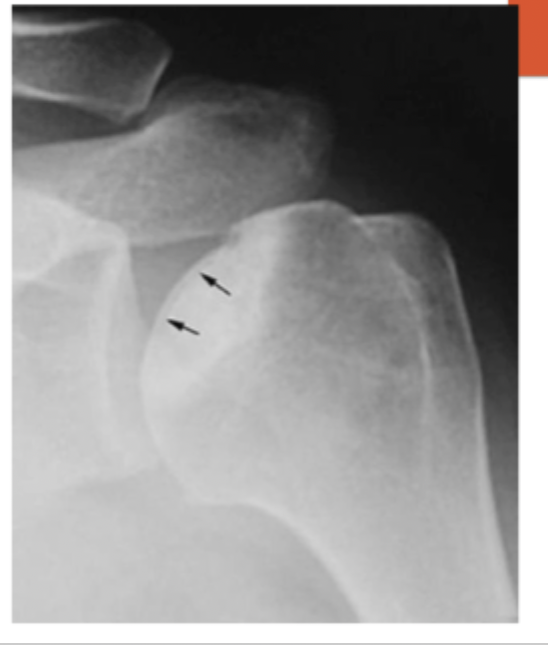

sclerosis in later stages → subchondral collapse

Signs of AVN on x-ray

normal xrays but MRI reveals death of the bone

Stage I of AVN is characterized by

Can be seen more on regular x-rays without collapse of the femoral head

Stage II of AVN is characterized by

xrays show signs of collapse “crescent signs”

Stage III of AVN is characterized by

x-ray has collapse and signs of cartilage damage (arthritis)

Stage IV of AVN is characterized by